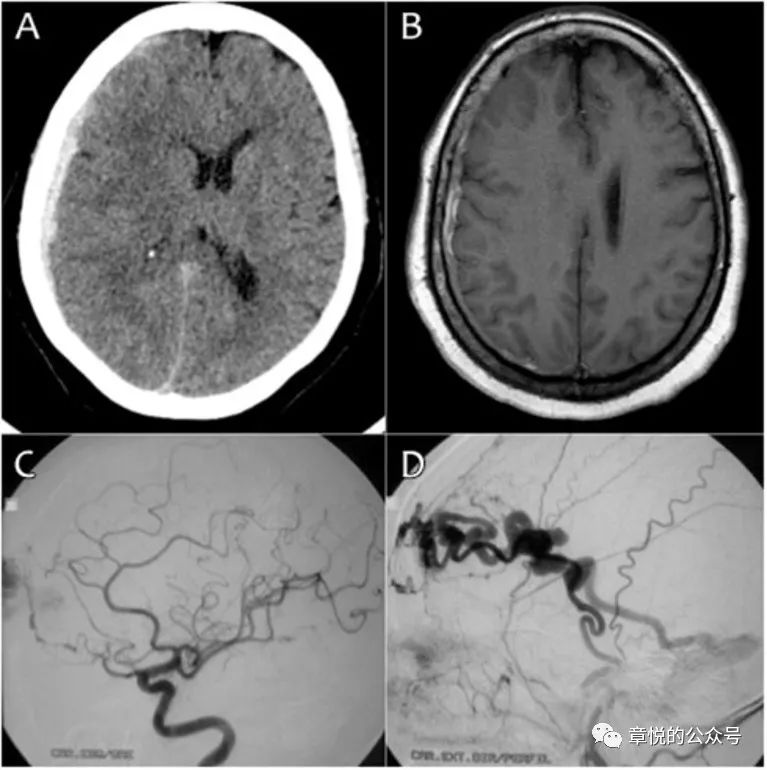

硬膜下血肿如破入蛛网膜下腔可导致蛛网膜下腔出血,蛛血引起的急性血管痉挛常在半小时以内出现,表现为头痛、局灶神经体征或一过性意识障碍;而迟发性血管痉挛常发生于出血的第3天,症状最严重为第6-8天,可持续2-3周,表现为头痛、意识障碍和/或局灶神经系统症状,血管造影可见血管痉挛收缩,MRI的弥散加权相(DWI)可见多发小梗死病灶。(图3)不过我们这个病例并不符合上述影像表现:MR并未见到梗死病灶;CTA也没见到血管痉挛;而腰穿直接否定了血管痉挛的前提——蛛网膜下腔出血,腰穿连一个红细胞都没捞着。

图3. 蛛网膜下腔出血导致的血管痉挛及DWI相所见的病灶

硬脑膜动静脉畸形(dural arteriovenous malformation,DAVM)是硬脑膜内的动静脉沟通或动静脉瘘,由硬脑膜动脉或颅内动脉的硬脑膜支供血,并回流至静脉窦或动脉化脑膜静脉,DAVM的其中一个原因就是脑外伤。在既往文献中有过硬脑膜动静脉瘘导致硬膜下血肿的案例。DAVM的出血通常位于蛛网膜下腔,少数为脑内,出在硬膜下十分罕见。(图7)

图7 60岁女性,因昏迷送院,当她醒后表现为意识混乱和头痛。CT和磁共振见硬膜下血肿,脑叶肿胀明显。DSA可见硬脑膜动静脉瘘。de Aguiar GB,et al. Spontaneous acute subdural hematoma: A rare presentation of adural intracranial fistula. J Clin Neurosci. 2016,25:159-160